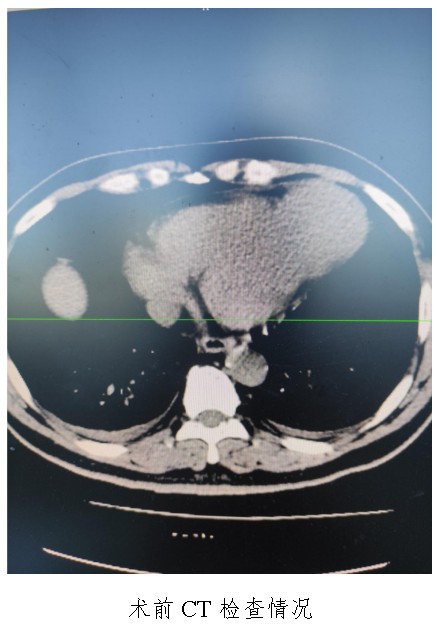

通訊員廖金文報(bào)道:一名50歲左心室前壁中下段及心尖部巨大室壁瘤患者在衡陽市中心醫(yī)院心胸外科廖金文主任、屈云劍副主任團(tuán)隊(duì)的精心治療下,接受左心室室壁瘤切除加左心室修補(bǔ)成型手術(shù)后,恢復(fù)良好,于11月1日出院。

10月18日,50歲的孟先生因反復(fù)胸悶氣促一周,夜間不能平臥來衡陽市中心醫(yī)院心胸外科就診,經(jīng)心臟超聲檢查提示左心室前壁中下段及心尖部巨大室壁瘤,66×57mm,最薄處約3mm?;颊哂卸嗄晏悄虿〔∈?,既往有無癥狀心肌梗死病史,曾行PCI治療。入科后,廖金文主任、屈云劍副主任組織心內(nèi)、麻醉、體外循環(huán)、重癥醫(yī)學(xué)科對(duì)病人病情進(jìn)行了多學(xué)科討論,一致認(rèn)為手術(shù)是治療該病例的唯一手段。經(jīng)過充分的術(shù)前準(zhǔn)備,10月24日,心臟外科團(tuán)隊(duì)給患者實(shí)施了左心室室壁瘤切除加左心室修補(bǔ)成型手術(shù),手術(shù)順利,術(shù)后經(jīng)過精心的治療管理,患者恢復(fù)良好,康復(fù)出院。該病例的手術(shù)成功,不僅是術(shù)中及手術(shù)團(tuán)隊(duì)智慧的結(jié)晶,也是多學(xué)科合作的結(jié)果,展示了衡陽市中心醫(yī)院處理復(fù)雜危重患者的能力。